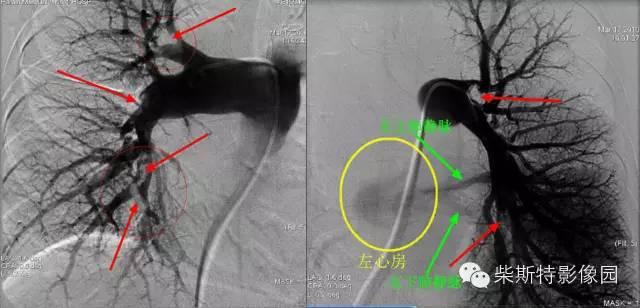

第一大名捕:肺动脉造影

红色箭头所指处即为栓子导致的充盈缺损。尽管肺动脉造影目前已经被肺动脉CTA所替代,但是其“老大”的地位还是无法撼动!

“老大”的绝招是其不仅可以提供整体的肺血管的解剖学资料,而且可以提供血流动力学参数,即可以用于诊断也可以用于治疗,如急性肺栓塞的导管内局部溶栓、捣栓、碎栓、抽栓,先天性肺动脉狭窄的球囊扩张、支架植入、肺动静脉瘘的栓塞治疗等。

第四大名捕:肺通气灌注扫描

肺灌注显像:溶栓前(上图)和溶栓后(下图)

肺通气灌注扫描的本领也是不容小视!尽管排名第四,但有时候前三位“大哥”破不了的案,还要依赖于这个“四弟”!